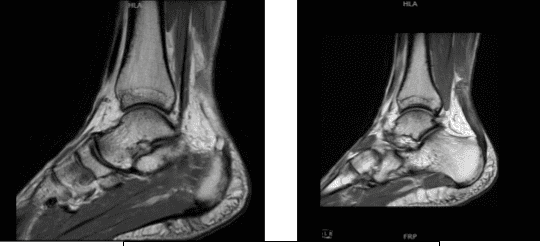

MRI were reviewed and discussed, the soft tissues have significant posterior soft tissue swelling and edema secondary to Achilles tendon pathology. The bone marrow has a mild edema in the anterior tibial plafond and. No fracture or avascular necrosis.

While the osteochondral lesion is none, the medial tendons-posterior tibialis tendinosis and tenosynovitis without tears and the remainder the medial tendons, anterior tendons and lateral tendons are unremarkable.

The lateral ligaments: Syndesmotic ligaments: evidence of remote sprain and thickening of the anterior tibiofibular Ligament. No acute syndesmotic injury. Anterior talofibular ligament: evidence of remote sprain with mild thickening and scarring but no acute injury.

Calcaneofibular ligament and Posterior talofibular ligament are unremarkable. Medial ligaments: Deltoid ligament, Tibio-spring ligament, Proper spring ligament are unremarkable. Lisfranc ligament and joint are both normal.

The Achilles Tendon: Full-thickness tear of the Achilles tendon 4.3 cm proximal to its attachment near the myotendinous junction/aponeurosis with significant underlying, the Tendinosis and marked thickening of the Achilles tendon with a 1 cm gap in the torn tendon fibers.

The Plantar Aponeurosis: Thickening of the central cord of the plantar aponeurosis without Edema compatible with the sequelae of prior plantar fasciitis which is now healed. Sinus Tarsi: Normal fat signal characteristics. Tarsal Tunnel: Normal without masses. Muscles: Normal signal and bulk without edema or atrophy.

Marked Achilles tendinosis with a full-thickness tear 4.3 cm proximal to its attachment at the myotendinous junction with a 1 cm gap and associated soft tissue swelling. Posterior tibialis tendinosis and tenosynovitis without tears.

Evidence of remote syndesmotic ligament sprain and remote anterior talofibular ligament sprain but no acute ligamentous injury. Sequelae of healed plantar fasciitis.

MRI-1.2T Left ankle non-contrast